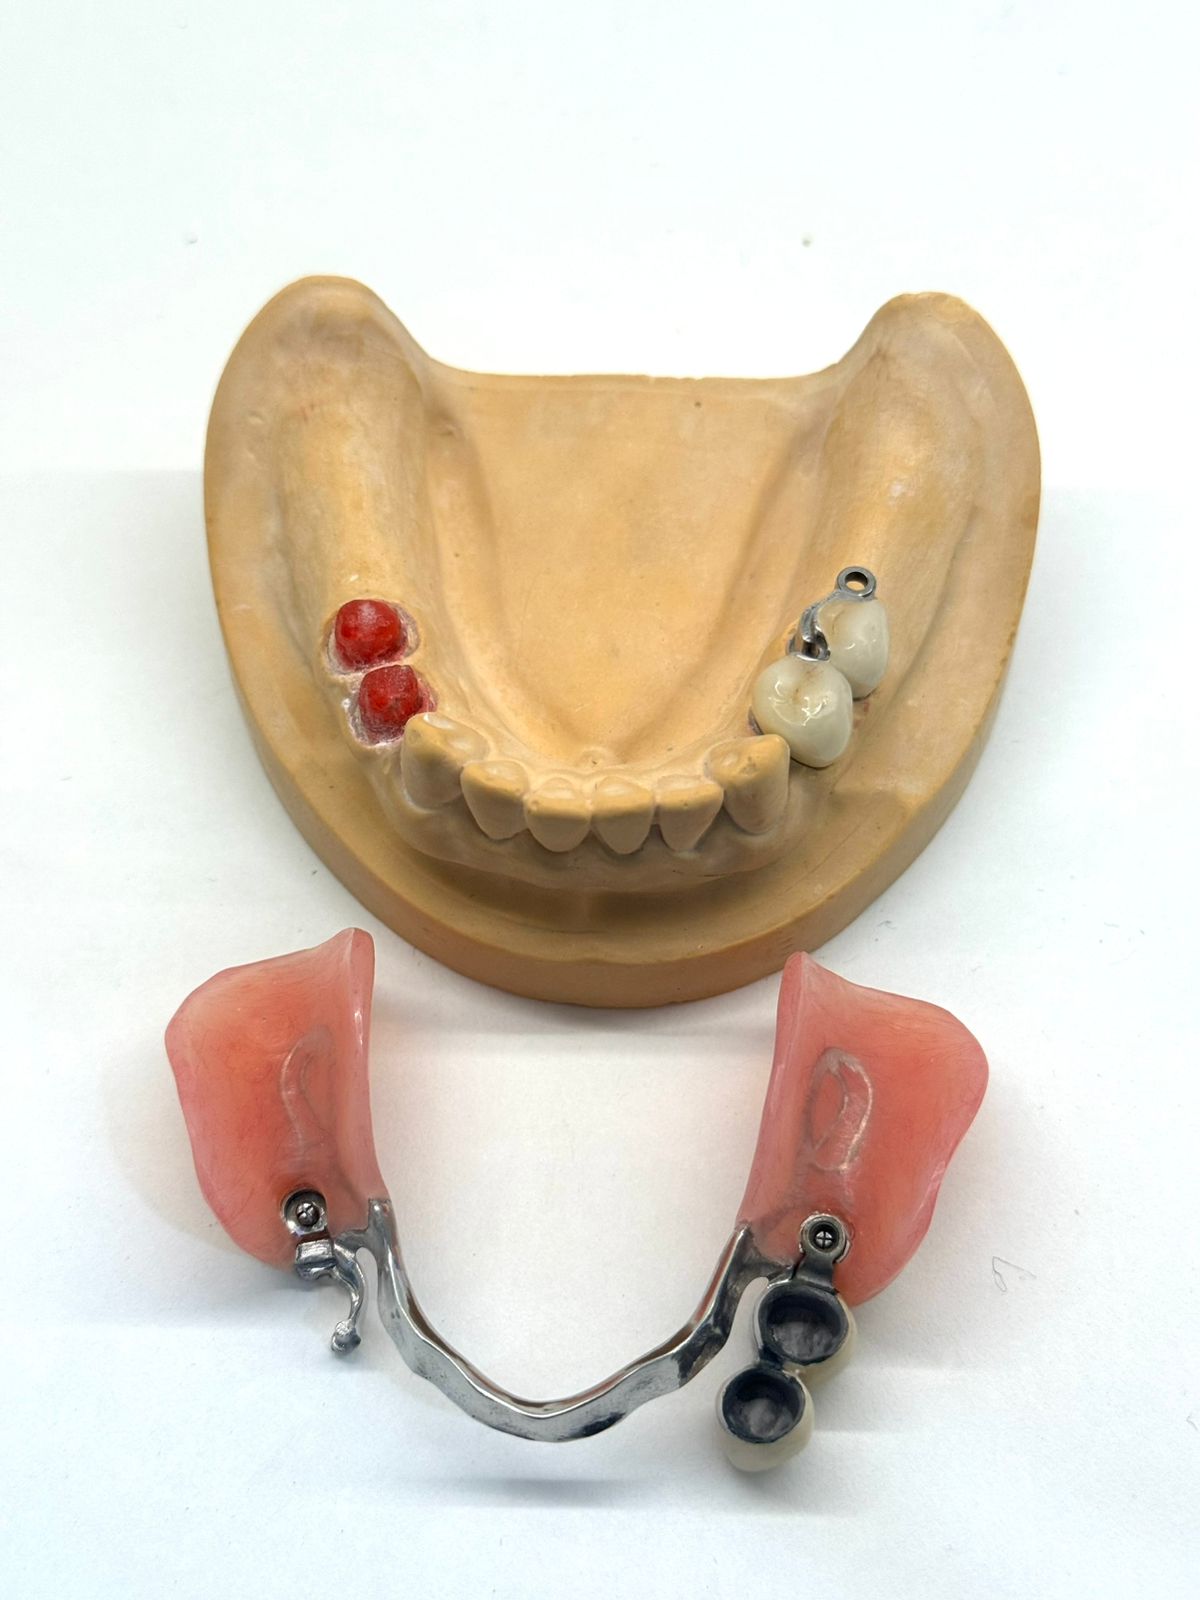

Примеры съемных зубных протезов в Хуньчуне

Съемные зубные протезы в Хуньчуне: виды, материалы изготовления, особенности выбора

Кому подходит: при полном или частичном отсутствии зубов. Подходит также пациентам с выраженной атрофией костной ткани, когда имплантация затруднена или временно не планируется.

Противопоказания: при наличии аллергии на металл используются конструкции без металлического каркаса — из современных гипоаллергенных материалов.

Сроки: изготовление и установка занимают 2–4 дня.

Гарантия: от 3 до 10 лет (у разных клиник).Стоимость от 25 000 рублей зависит от модели.